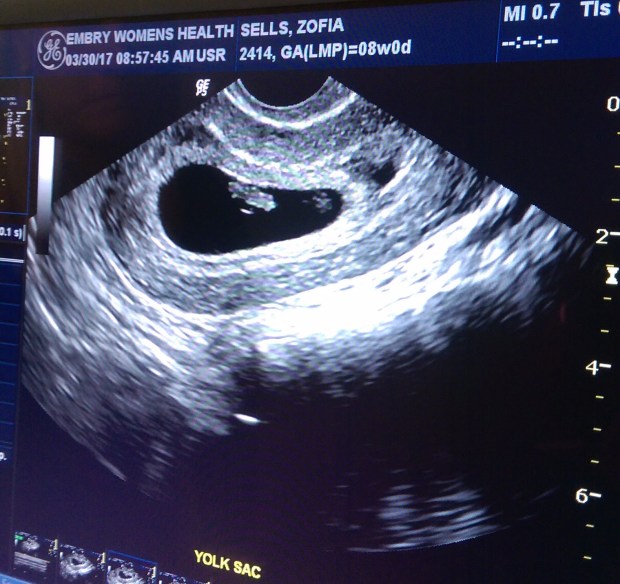

My mother-in-law has quite a few more grand kids than my mom (about 7 more to be precise) so we figured her reaction might be slightly different. A few years back we had gone on a trip with her to search for her biological father and came up empty handed. Well, fast forward to present day, and we learned that she had finally found him and other family through an ancestry website. We were so thrilled and excited for her that after all these years, she had finally found him. What was even more exciting to us is that our baby, who she didn’t know about yet, would be born into this world with a whole other side of family that we hadn’t known before. One night, we went over to her house to talk about what she had discovered and what new family members she had found. We saw of a picture of her biological father, and other family. The resemblance was uncanny. Although we learned he had died in 2006, we were so happy that we had finally learned who he was. Leaving her house that night, Zarin and I looked at each other and realized we couldn’t wait to tell her. So we went back to the door and rang the doorbell. She answered and we stood there frozen. I nudged Zarin to say something and she stared back at us asking what was wrong. He lifted up his cellphone with the picture of our first ultrasound. She looked more closely and said, “You pregnant!?” We both smiled and nodded yes and she let out a big smile and hugged us both. We told her how excited we were to learn about our baby’s great, great grandpa and that the timing of her finding him and us finding out about our baby we’re too perfect.

During our 12 week ultrasound the baby was very active! As soon as the ultrasound tech put the wand on my stomach, we could see the baby spinning and flipping around. We tried to get some close photos of baby’s face, but baby kept hiding behind his/her arms. We did, however, get a perfect profile picture of Baby Sells and I fell in love. I can’t wait to feel baby’s first move! We also got lucky at our 14 week checkup with an unexpected ultrasound! My doctor was training a new staff member and had her sit in on our appointment. She explained that 14 weeks is one of the best times to see a baby because of the development and space that there still is in the womb. She asked if I would be okay having an ultrasound done to show her. Uh yes, any chance we have to see our baby we’d take it! We walked into the ultrasound room and got ready to see our baby. Right away we saw baby stretched all the way out rolling around and waving his/her arms. Our doctor kept mentioning how long the baby’s legs were. The baby kept doing jump squats. I have a feeling once I can start feeling him/her, it’s going to be nonstop! Then, we saw the baby opening and closing it’s mouth. Our doctor said it was the baby drinking the amniotic fluid. It looked like like a little pac man. My heart just melted.

Baby Sells at 12 weeks.

Hi Baby!